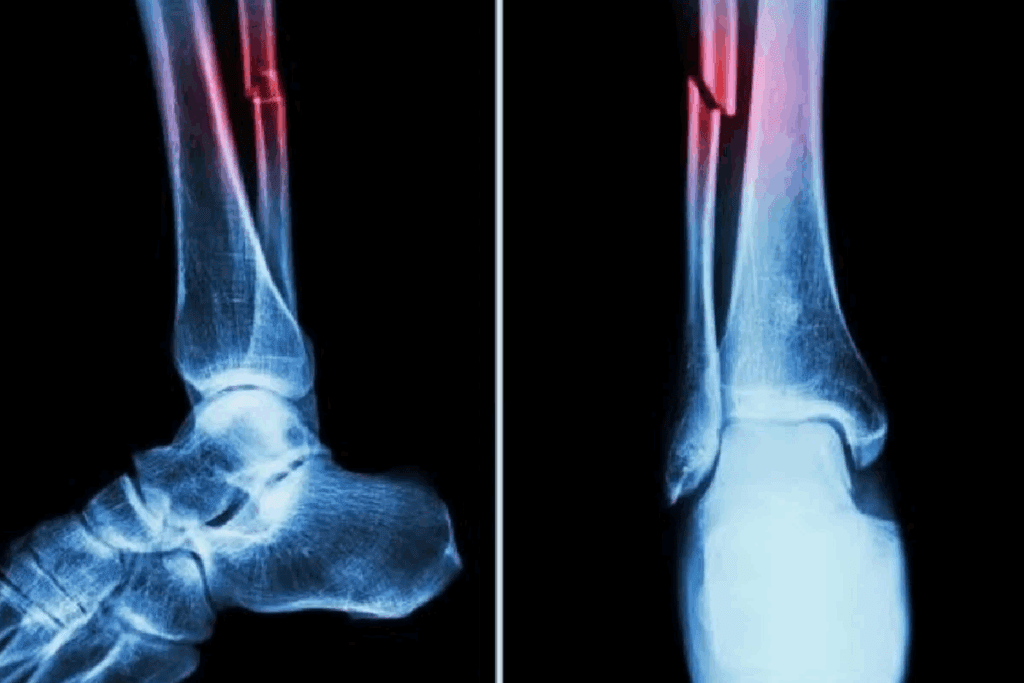

Imaging Techniques: X-rays, CT Scans, and MRIs

Imaging is key to confirming bone fractures. The right imaging depends on the fracture type, location, and patient’s health.

Common imaging techniques used include:

- X-rays: The first-line imaging modality for most suspected fractures, providing a quick and effective way to visualize bone structures.

- CT scans: Useful for complex fractures or when more detailed imaging is required, specially in cases involving multiple fragments or overlapping bones.

- MRIs: Particular value for detecting soft tissue injuries and stress fractures that may not be visible on X-rays.